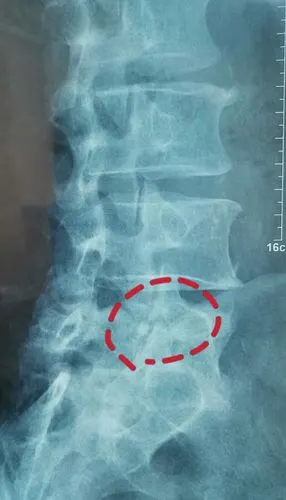

年轻人的发育不良性腰椎滑脱峡部裂应当引起重视